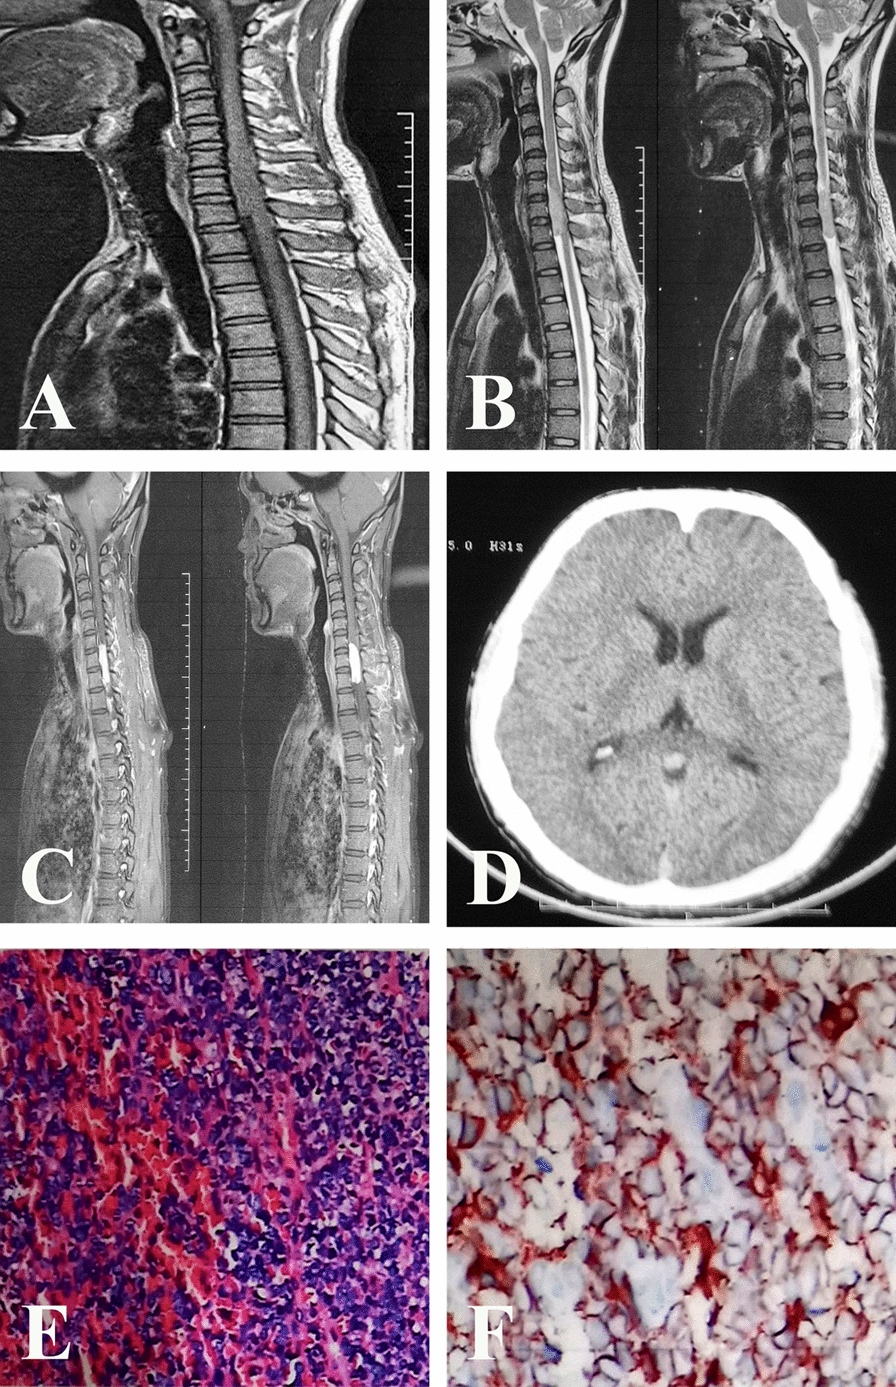

Case presentation: A 32-year-old male patient of Chinese ethnicity was diagnosed with a grade 2 intraspinal solitary fibrous tumor, demonstrating metastatic spread to the trigone region of the lateral ventricle. Despite cystic degeneration, the solid component of the metastatic lesion exhibited signal intensity similar to that of the primary tumor on imaging. A piecemeal gross total resection was achieved, and postoperative immunohistochemical analysis confirmed that the metastatic lesion was categorized as grade 3, with an increase in the Ki-67 proliferation index from 20% to 30%. Both the primary and metastatic tumors exhibited negative expression of CD34. Although radiotherapy was considered, consensus on its use was not reached, and the patient succumbed to tumor progression 17 months later.